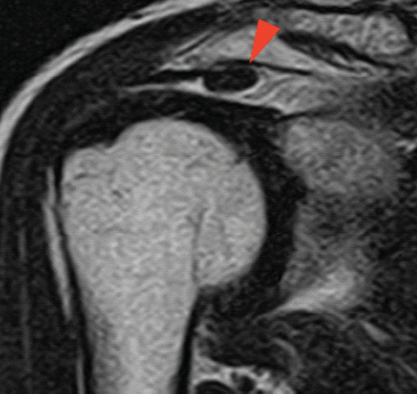

A 60-year-old man presented to our clinic with the right shoulder pain. On examination, his range of motion was 150° in forward flexion and 60° in external rotation, without mechanical catching. Magnetic resonance imaging (MRI) revealed a partial-thickness tear of the supraspinatus tendon (Fig. 1), and conservative management was initiated. However, as his nocturnal pain worsened, arthroscopy was performed 3 months later, confirming a partial tear. Arthroscopic rotator cuff repair was then carried out with augmentation using a medium-sized REGENETEN® implant, which was secured on the tendon surface (Fig. 2).

Figure 1: Pre-operative coronal T2-weighted magnetic resonance imaging (MRI) showing partial-thickness supraspinatus tear. Pre-operative coronal T2-weighted MRI of the right shoulder demonstrating a partial-thickness tear of the supraspinatus tendon (arrowhead). The image was obtained before any intervention.